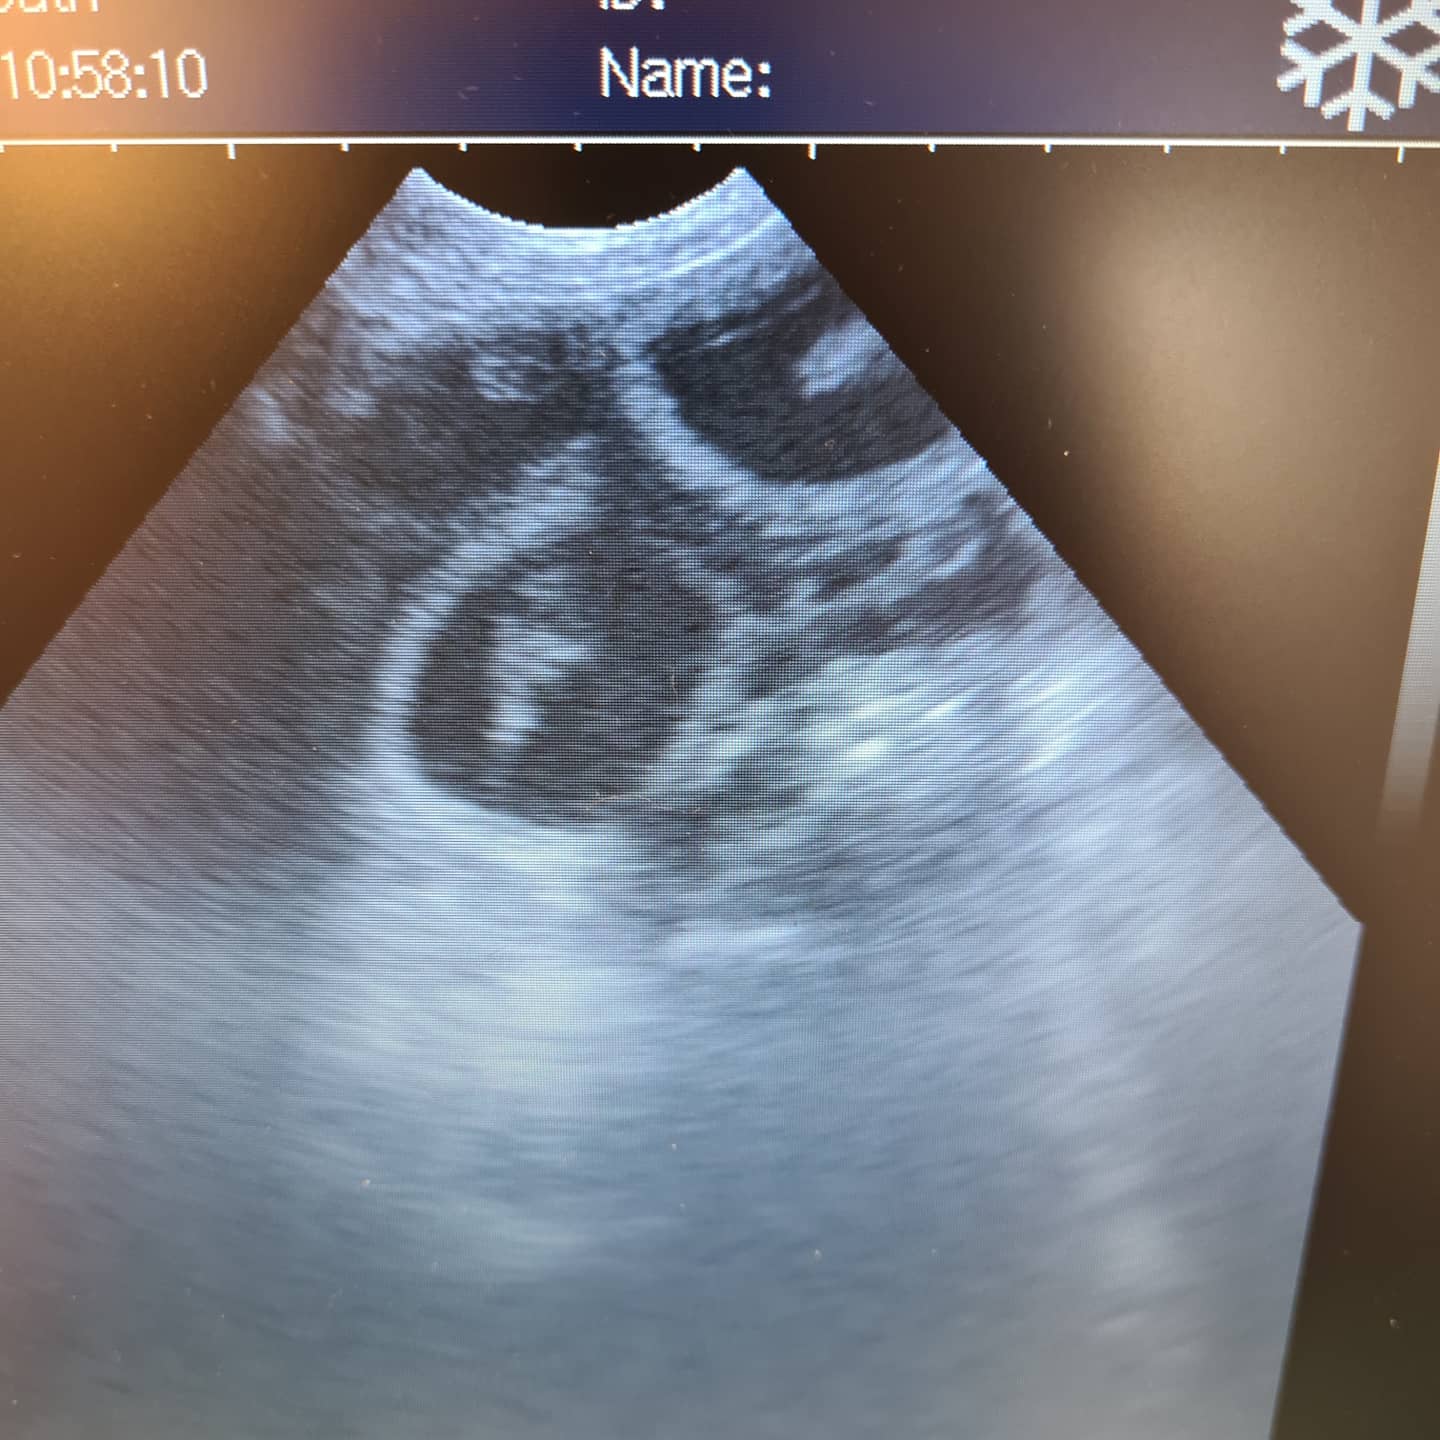

Wire haired fox terrier day 35 (40 days from last tie) good example of how sperm can hang around awhile before fertilisation occurs . Gestational sacs developing well just not